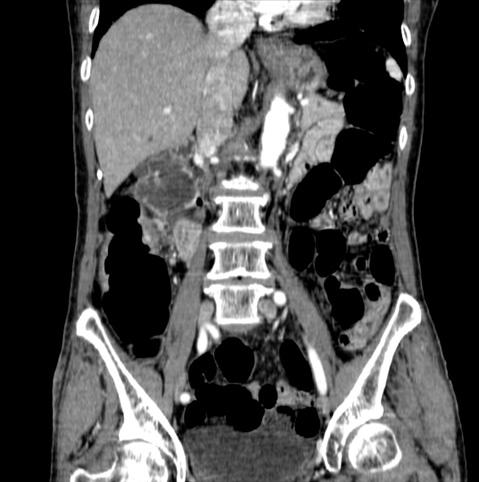

Tuberculosis del Colon que mostró en su esta primaria la semejanza a O-IIc

Enfermedad Inflamatoria - Ulcerativa/Tuberculosis

colon/ascendente

Resonancia Magnética

40 -